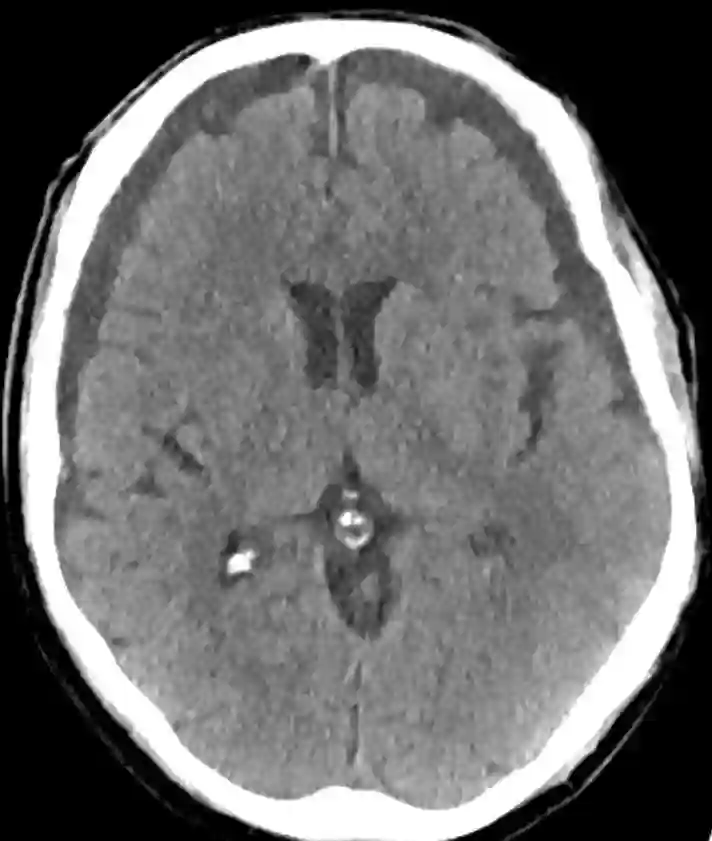

Ein weiterer wichtiger Faktor bei der Entstehung von Hygromen ist die Liquordynamik. In einigen Fällen kann es bei Patienten mit einer Liquorableitung, wie zum Beispiel einem ventrikuloperitonealen Shunt (VP-Shunt), zu Komplikationen kommen. Ein VP-Shunt ist ein chirurgisch eingesetzter Katheter, der dazu dient, überschüssigen Liquor aus dem Ventrikelsystem in andere Körperregionen abzuleiten, um so den intrakraniellen Liquordruck zu reduzieren. Ist dieser Shunt nicht richtig eingestellt und leitet zu viel Liquor ab, kann dies zu einer Unterdrainage führen, die wiederum ein Hygrom verursachen kann[^2].

In der CT- oder MRT Bildgebung, äußern sich Hygrome oft als flüssigkeitsgefüllte Räume, die ähnlich wie chronische Subduralhämatome aussehen.

In der MRT bieten sie ein etwas anderes Bild, abhängig von der spezifischen Zusammensetzung der Flüssigkeit und den verwendeten Sequenzen. Die genaue Unterscheidung zwischen einem subduralen Hygrom und einem chronischen Subduralhämatom kann jedoch schwierig sein, da beide Krankheitsbilder in der Bildgebung sehr ähnlich aussehen können.